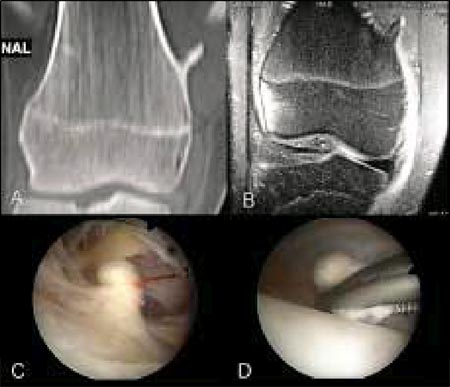

Caso 2: Paciente de sexo masculino de 18 años de edad. A: Corte frontal de la Tomografía Axial Computada del fémur distal, con una exostosis en cara interna del mismo. B: Resonancia Magnética Nuclear en la cual se observa la localización extraarticular del osteocondroma. C: Imagen artroscópica del tumor luego del debridamiento capsular. D: Visión artroscópica de la resección del osteocondroma con una pinza de prensión.